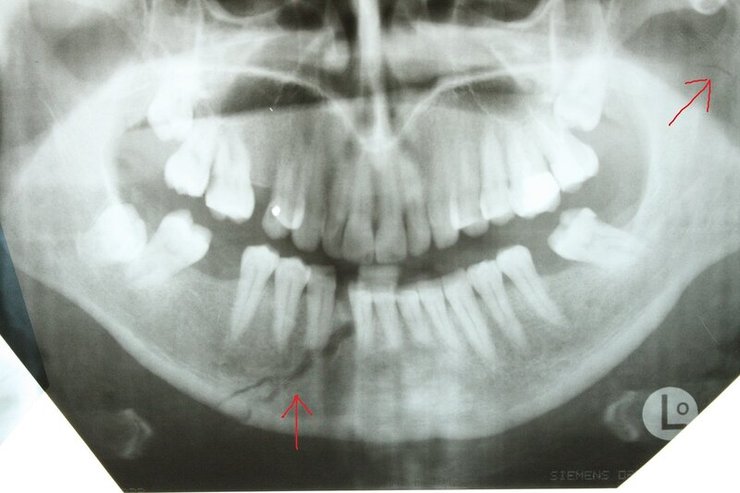

Щелепа Адама Кадирова Фото: NIYSO

Автори вказують, що притаманна для подібної травми припухлість обличчя зникає лише за тиждень-два. А щоб зняти фіксацію щелепи, знадобиться приблизно місяць.

Також внаслідок зіткнення в Кадирова-молодшого могли з’явитися рвані рани, порізи, тріщини шкіри та синці. З цієї причини може знадобитися ще декілька тижнів, щоб приховати наслідки інциденту.